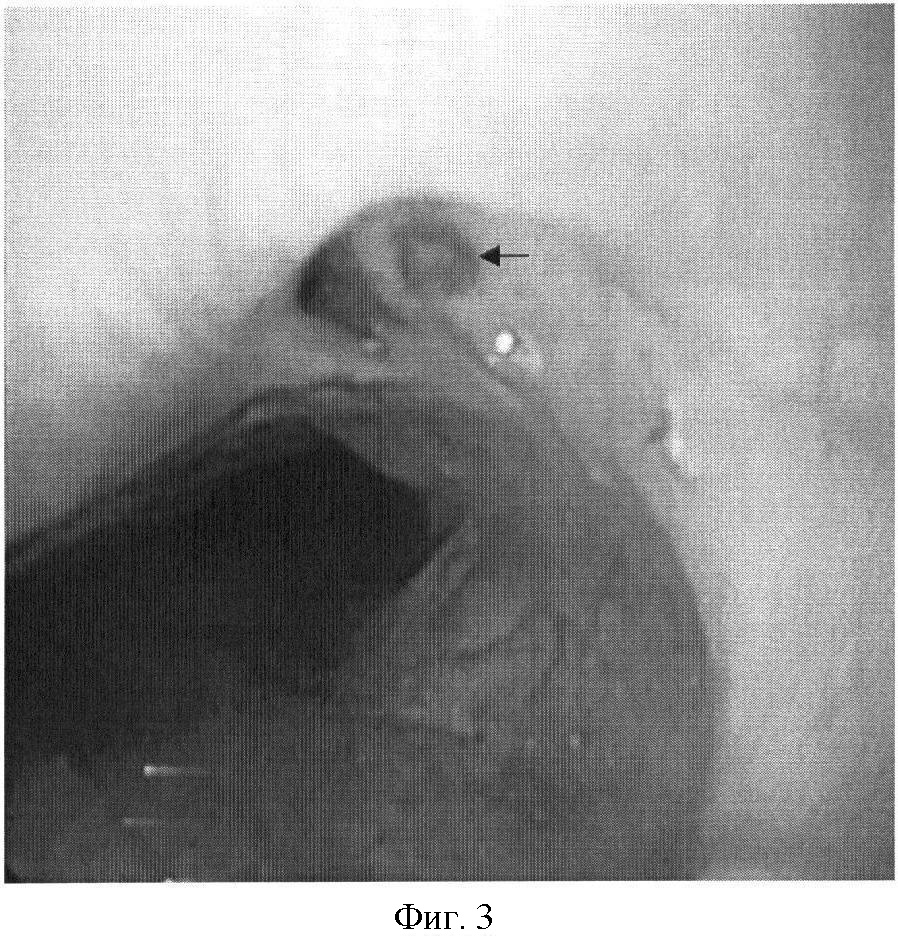

На фиг.1 представлена рентгенограмма пищевода с контрастным веществом: определяется контрастирование трахеопищеводного свища. На фиг.2 представлена эндоскопическая картина просвета пищевода: устье трахеопищеводного свища указано стрелкой. На фиг.3 представлена эндоскопическая картина просвета пищевода: предварительно в устье трахеопищеводного свища, открывающегося в просвете трахеи, было ведено 0,8 мл красящего вещества (метиленовой сини), после этого в просвете пищевода определяется прокрашивание устья трахеопищеводного свища (указано стрелкой). На фиг.4 – пломбирование устья трахеопищеводного свища тахокомбом, предварительно устье свища было последовательно подвергнуто электрокоагуляции и химиокоагуляции (96% этиловый спирт). На фиг.5 – клиппирование запломбированного устья свища. На фиг.6 – контрольная эзофагоскопия, выполненная через 3 месяца после операции: в просвете пищевода в области устья трахеопищеводного свища определяются две скрепки. На фиг.7 – контрольная рентгенограмма после эндоскопического лечения (через 3 месяца): в области трахеопищеводного свища определяется незначительный дефект наполнения (указан стрелкой), трахеопищеводный свищ не контрастируется.